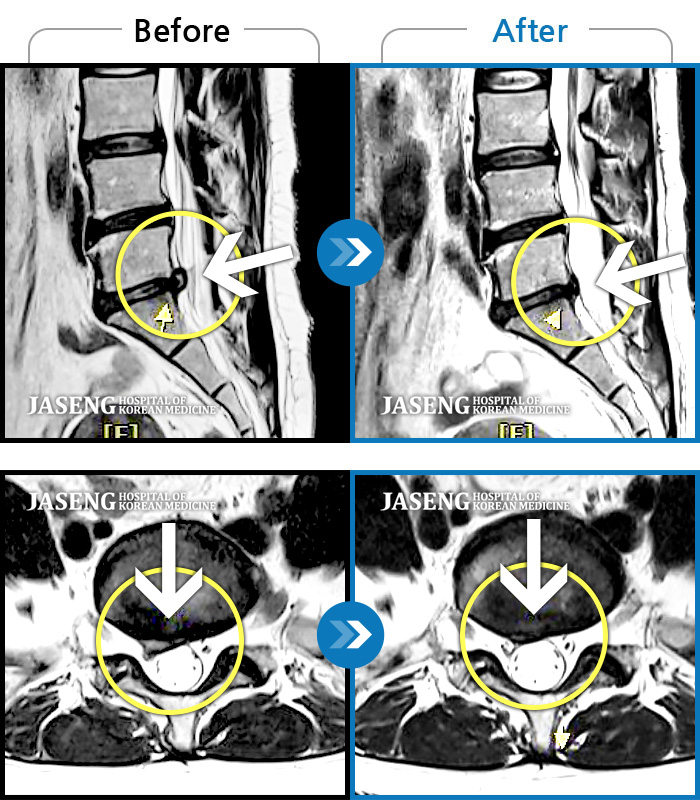

Before

After

좌측 허리 통증으로 허리를 반듯이 펴고 서있기 힘들어 내원하셨습니다.

2024.08.12 ~ 2025.02.26